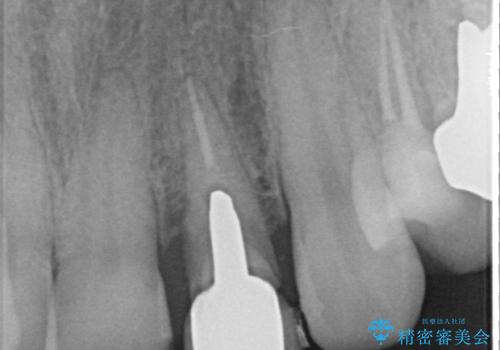

左上4、5番目の歯は根尖病変を認めたため再根管治療を行い、オールセラミッククラウンによる補綴を行いました。

なお左上4に関しては縁下歯質を改善するため、歯冠挺出を行っております。

- 根管治療により痛みや腫れがひかない事や、術後に痛みや腫れが生じる事、治療によるファイル破折やパーフォレーションなどの偶発症、術後の歯根破折を生じる可能性もあります